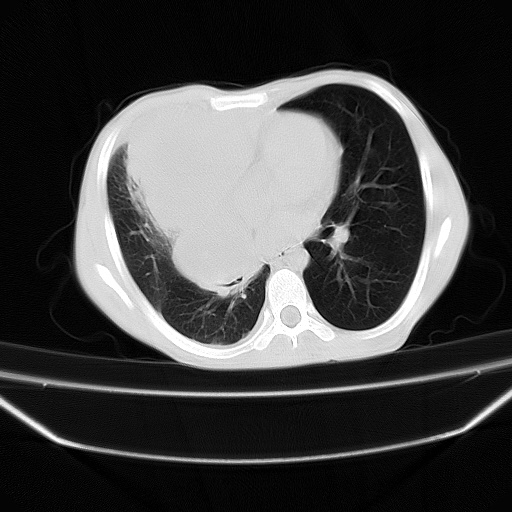

以下是引用zjzjr在2008-7-20 12:57:00的发言:[br]考虑为生殖源性肿瘤(内胚窦瘤),侵袭性胸腺瘤可能性大;右侧少量胸腔积液。

以下是引用xinliheng001在2008-7-20 21:17:00的发言:[br]右纵隔巨大分叶状软组织均质密度肿块,右上肺叶受压明显,纵隔右移、胸膜受累有少量积液和结节样增厚。应增强扫描一定会有更具诊断价值的信息。

以下是引用xinliheng001在2008-7-20 21:17:00的发言:[br]右纵隔巨大分叶状软组织均质密度肿块,右上肺叶受压明显,纵隔右移、胸膜受累有少量积液和结节样增厚。应增强扫描一定会有更具诊断价值的信息。